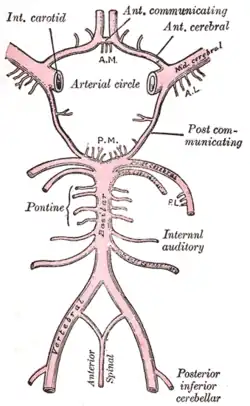

Die in der Neurologie wichtigsten Organsysteme sind das Zentralnervensystem (also Gehirn und Rückenmark), seine Umgebungsstrukturen und Blutgefäße. Dazu kommt das periphere Nervensystem und die Muskulatur, einschließlich der Verbindungsstrukturen zwischen beiden. In Deutschland ist die Neurologie um 1845 mit Moritz Heinrich Romberg als ein Teilgebiet aus der Inneren Medizin hervorgegangen. In den USA, in Großbritannien, Russland und anderen Staaten dagegen hatte sich die Neurologie gleich als eigenständiges Fach entwickelt.[1]

- Gefäßerkrankungen: hierzu zählen insbesondere der ischämische Hirninfarkt und die verschiedenen Formen der Hirnblutungen.

Die hirnversorgenden Gefäße können mittels Ultraschall (extrakranielle und transkranielle Doppler- und Duplexuntersuchungen) und invasiver Verfahren (z. B. Angiografie) untersucht werden.